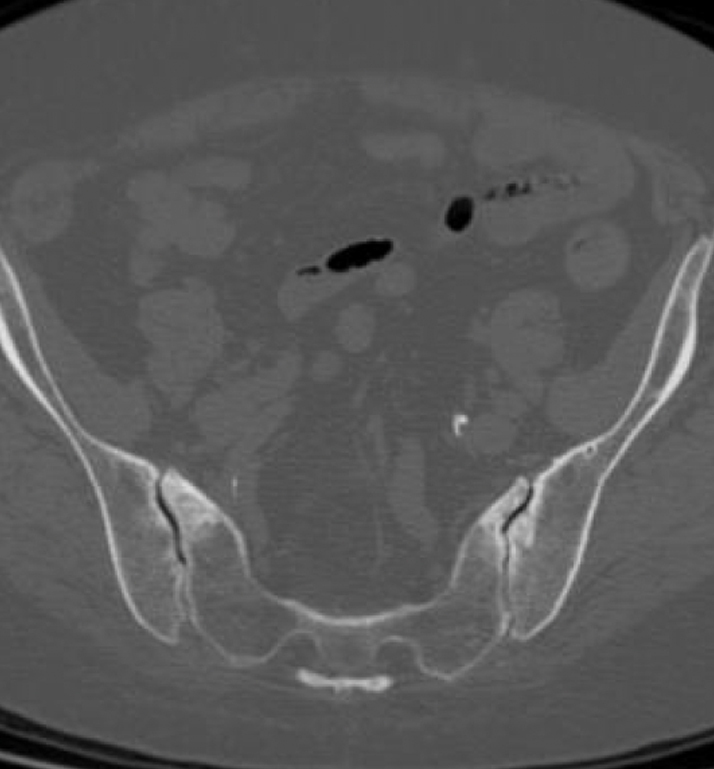

Bilateral Sacroiliac Joint Dysfunction Following L4-S1 Fusion

Patient Case History:

- High lumbar lordosis (77°) & pelvic incidence (86°)

- Spinal stenosis (L4-5) & radiculopathy (L5-S1)

- L4-5 & L5-S1 MIS transforaminal interbody fusion, November 2017

- Revision open L4-S1 fusion for pseudoarthrosis and hardware loosening, March 2019

- Bi-lateral SI joint degeneration with pain post revision surgery verified via SI joint block injection.

- CT of lumbar spine at +2 years post-op shows confirmation of the SI joint fusion.

Inline dennis 01